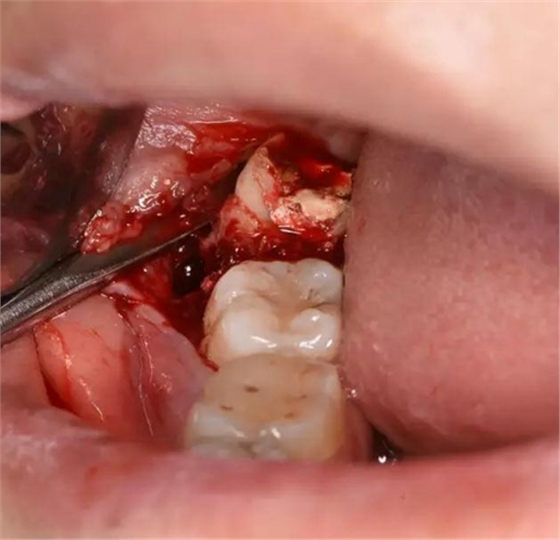

圖7.骨膜剝離器翻開牙齦、暴露48合面

圖8.近中放置牙挺、挺松48